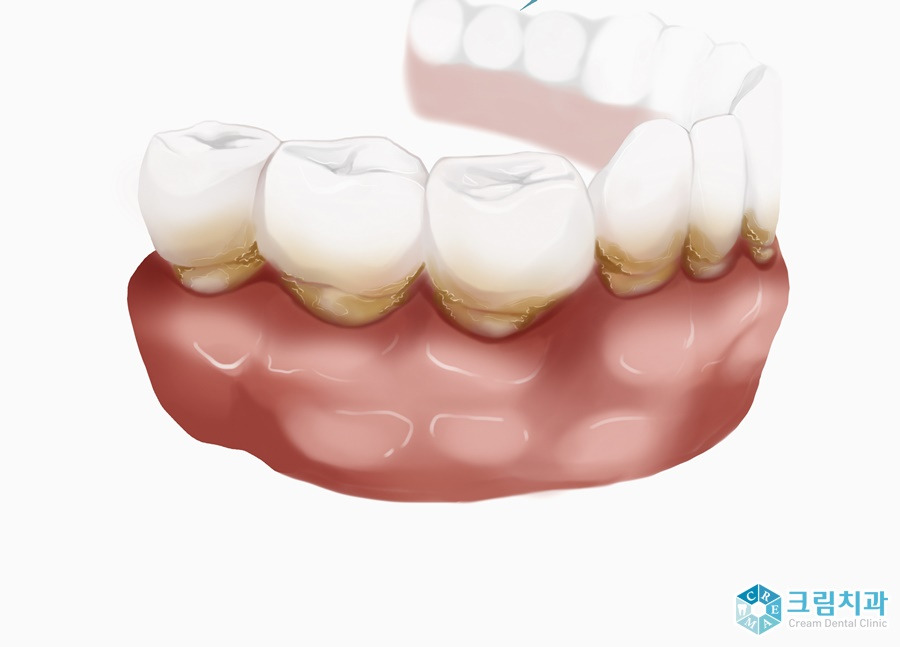

치주질환이 점차 진행되면 치아 주변의 치조골이 소실되면서 치아가 하나 둘 빠지기 시작하는데요. 이렇게 치아가 많이 상실되면 상실된 치아를 대체할 수 있는 치료를 진행해야 합니다.

전체적으로 치아를 상실했을 때 자연치아와 가장 근접하게 그 기능을 회복시켜주는 것이 바로 전체임플란트인데요.

전체임플란트는 임플란트 시술 중에서도 고난도 치료에 해당되기 때문에 진단부터 시술, 그리고 사후 관리까지 철저하게 고려해 치과를 선택해야 합니다.